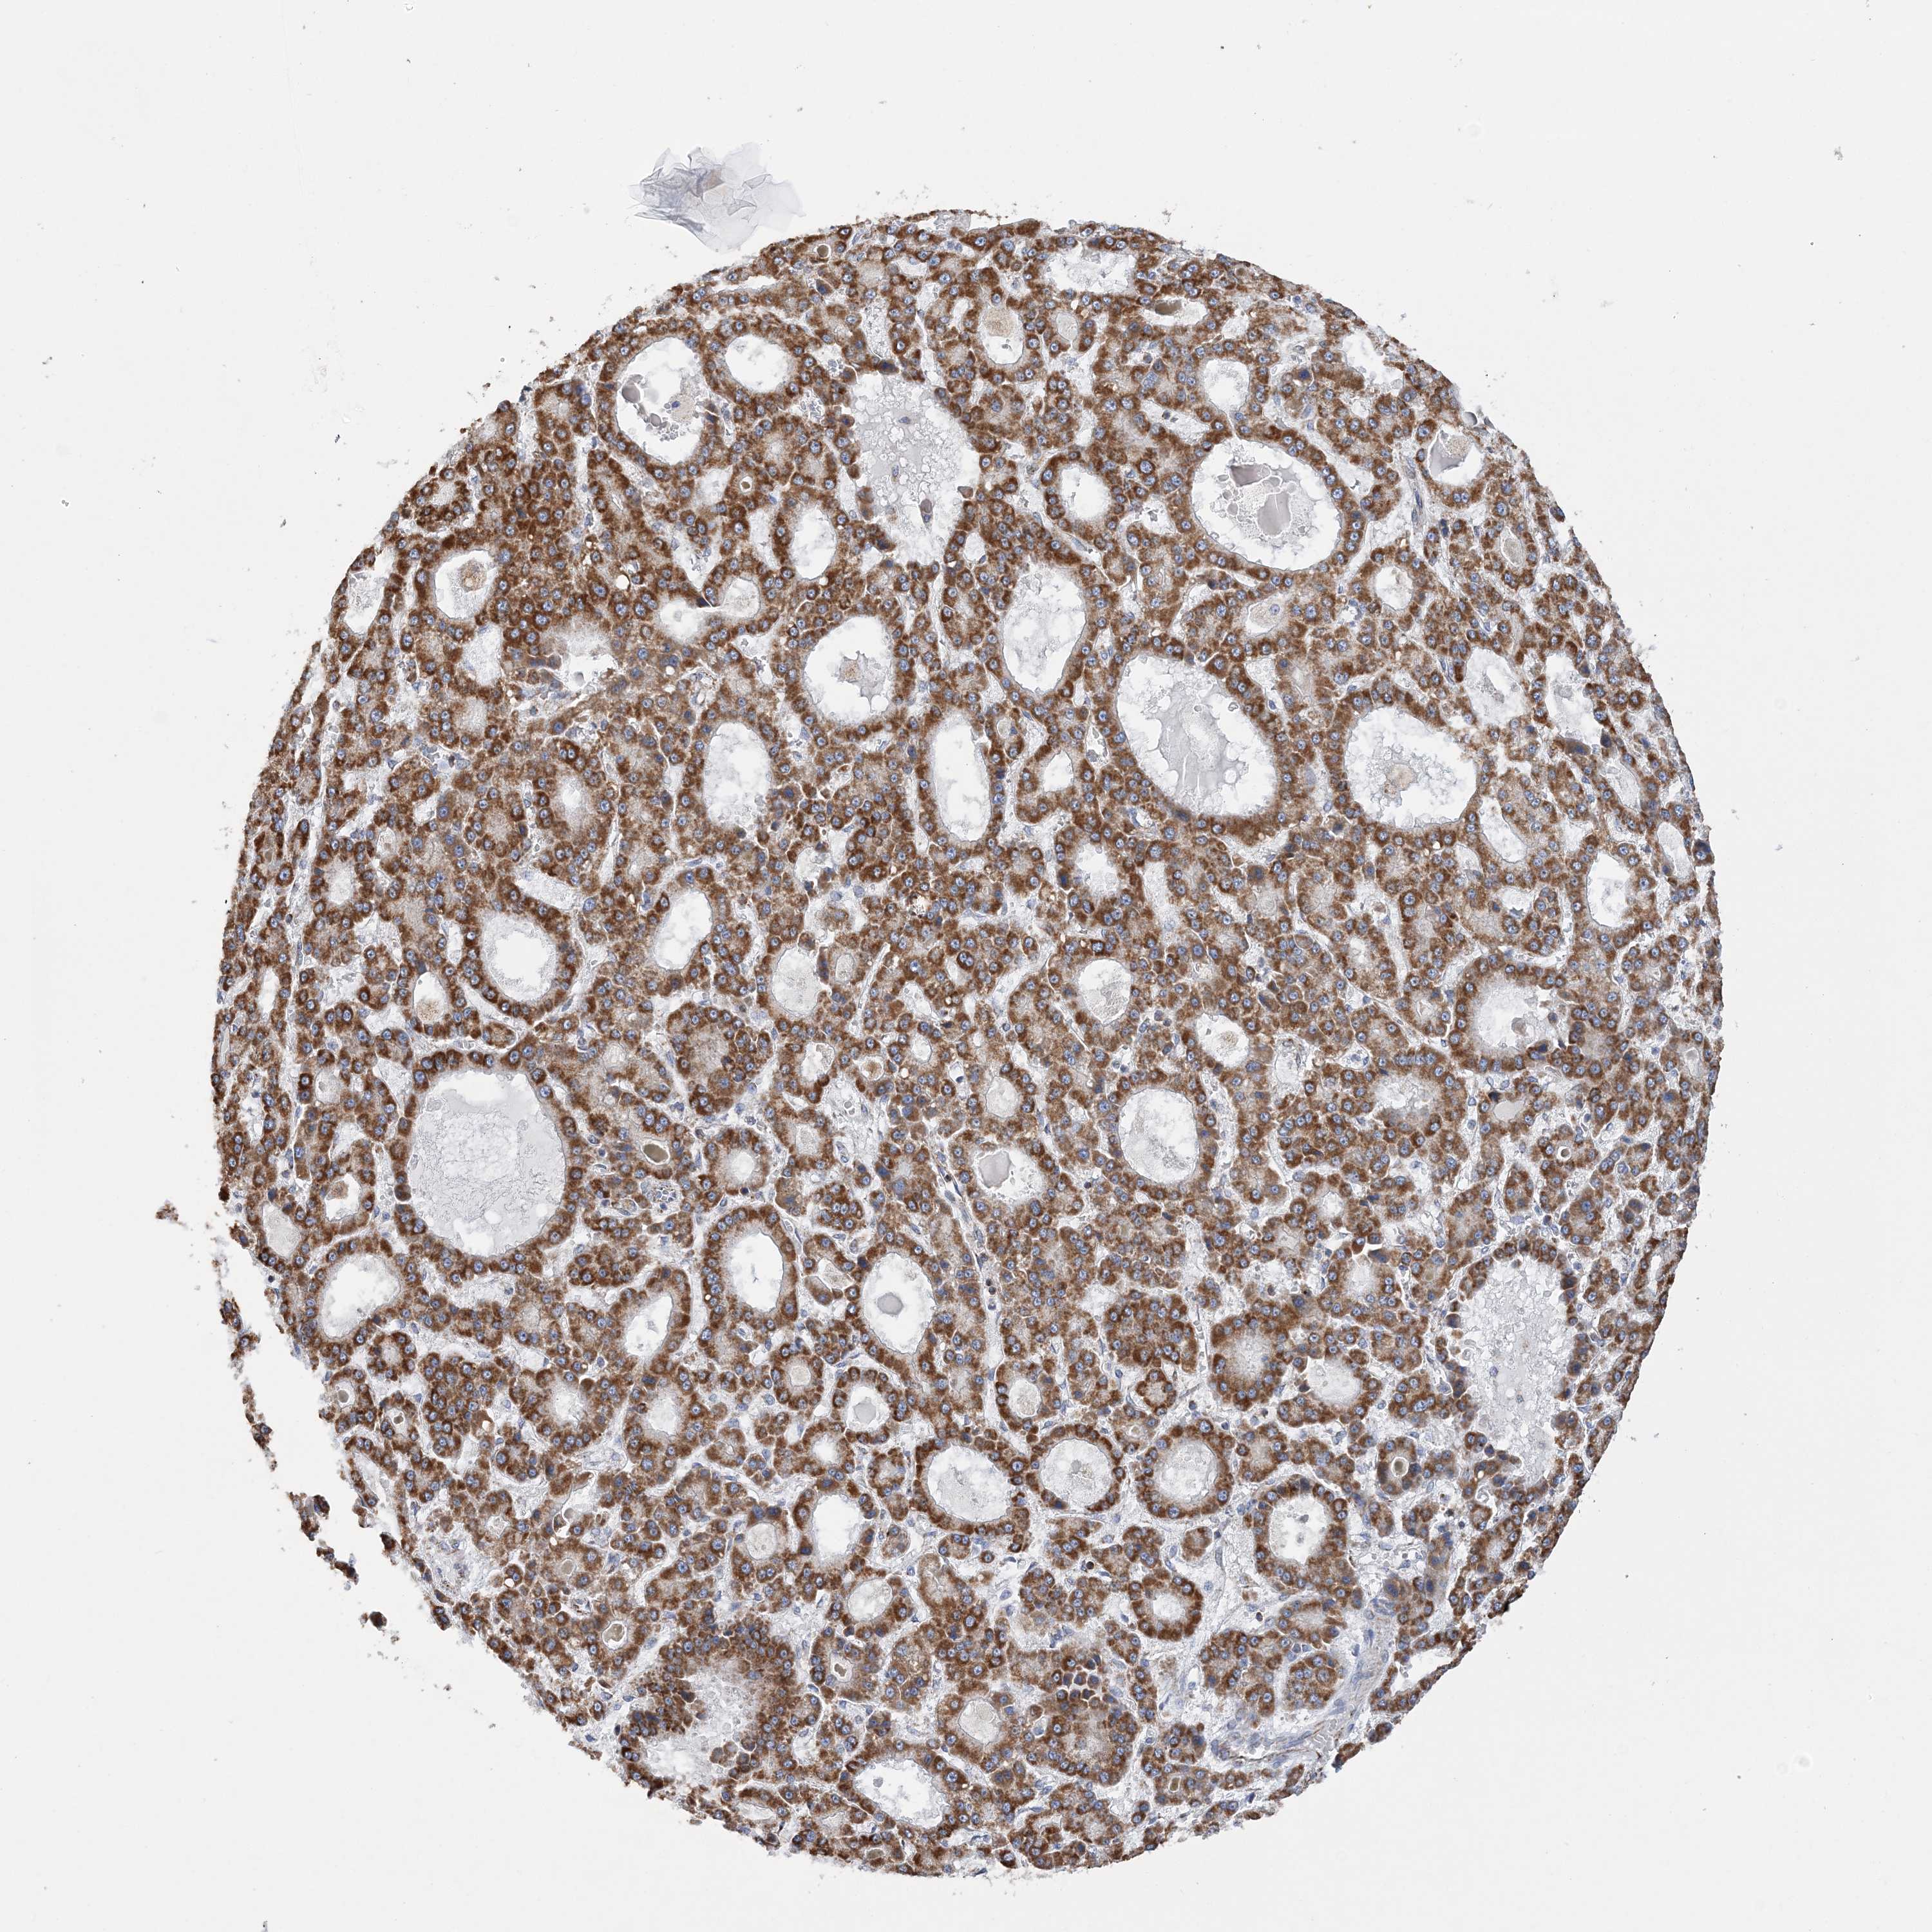

LIVER CANCER - Protein expressioni

A mouse-over function shows sample information and annotation data. Click on an image to view it in a full screen mode. Samples can be filtered based on level of antibody staining by selecting one or several of the following categories: high, medium, low and not detected. The assay and annotation is described here.

Note that samples used for immunohistochemistry by the Human Protein Atlas do not correspond to samples in the TCGA dataset.

Antibody stainingi

Antibody staining in the annotated cell types in the current human tissue is reported as not detected, low, medium, or high, based on conventional immunohistochemistry profiling in selected tissues. This score is based on the combination of the staining intensity and fraction of stained cells.

Each image is clickable and will lead to virtual microscopy that enables deeper exploration of all samples and also displays staining intensity scores, fraction scores and subcellular localization as well as patient and tissue information for each sample.

Antibody HPA036024

Staining

High

Medium

Low

Not detected

Intensity

Strong

Moderate

Weak

Negative

Quantity

>75%

75%-25%

<25%

None

Location

Nuclear

Cytoplasmic/membranous

Cytoplasmic/membranous,nuclear

Cholangiocarcinoma

Carcinoma, Hepatocellular, NOS